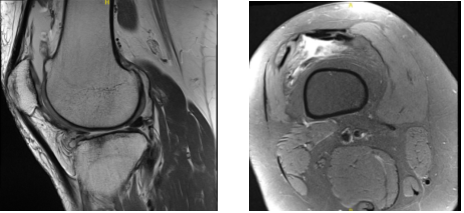

MRI were presented and found horizontal tear anterior horn and body lateral meniscus with intrasubstance meniscal cyst contiguous with the anterior 1 tear and edema in the anterior infrapatellar fat.

Lateral subluxation patella with patellofemoral arthrosis with Joint effusion with synovitis were observed. Also, her hamstring and gastrocnemius tendinopathy with medial bursitis.